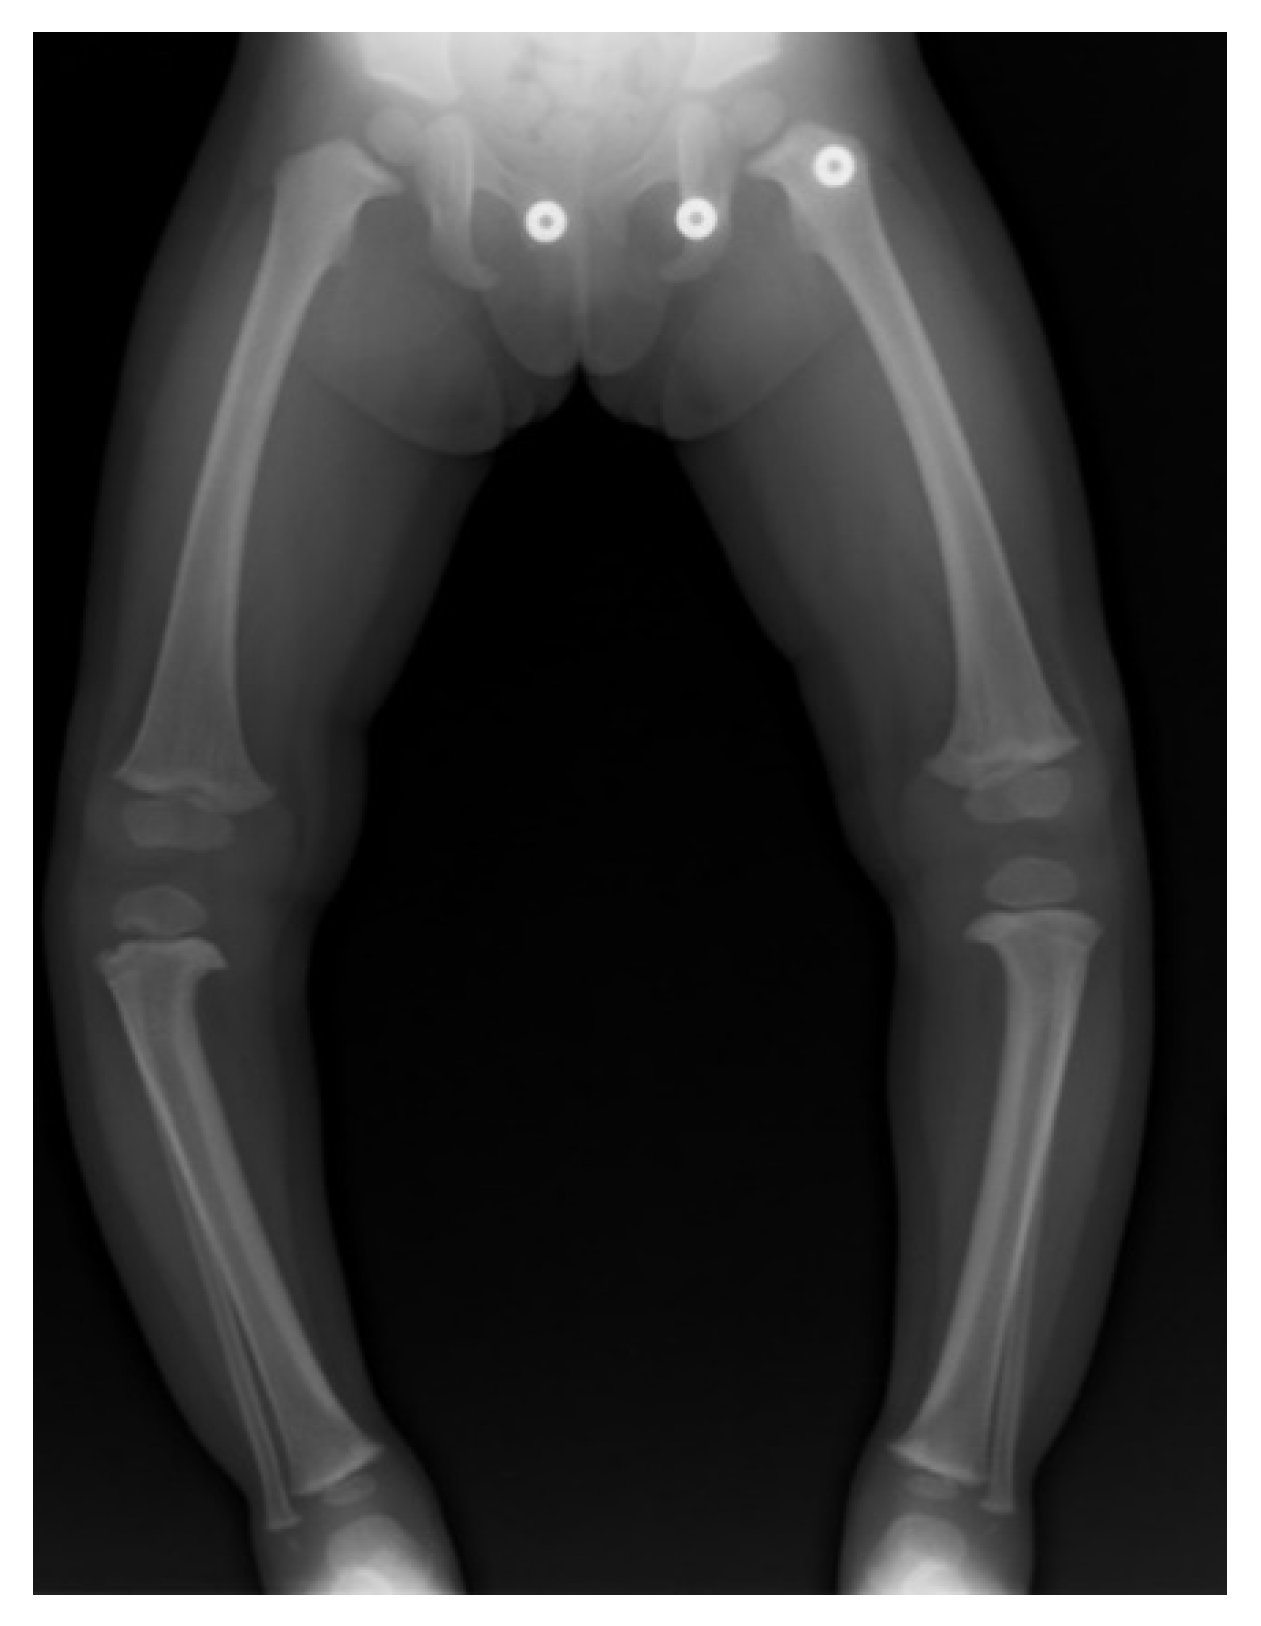

3. ITV Differential Diagnosis and Clinical Features

4. Radiographic Imaging

17. Gradual Correction with External Fixation